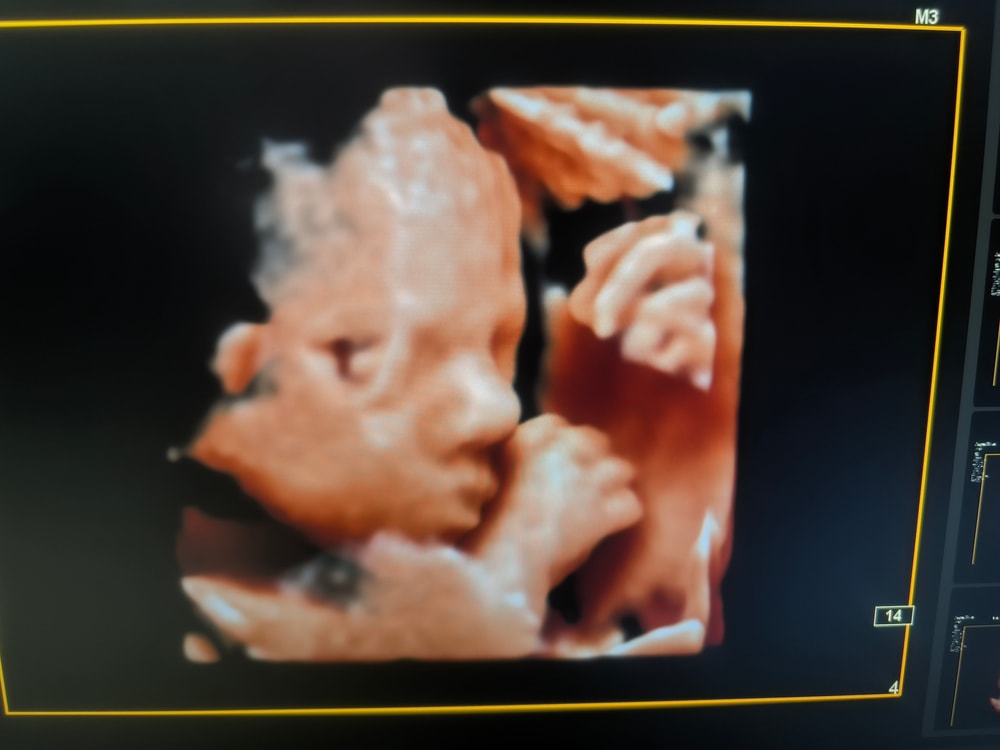

Узи 27и6 недель

Съездили сегодня на узи в Днк клиник по рекомендации девушки к Горяиновой . Оооочень понравилась, теперь она мой топчик. 😍

Бусинка наша 1097 гр. Все развито по срокам, все в норме 🙏Волос сказали мало пока, только только пушок вылез, но возможно вырастут еще, у старших детей длиннющие шевелюры были.

Так интересно наблюдать как дети там существуют ... Чудо техники все же 😀